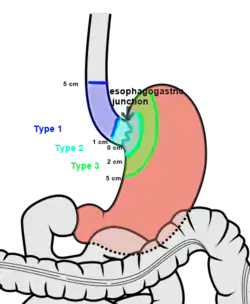

The Siewert-Stein classification (often called the Siewert classification in less precise shorthand reference) is a system of anatomical classification used for adenocarcinomas of the esophagogastric junction.

Type I

Adenocarcinoma of the distal part of the esophagus. The tumor center is located 1–5 cm above the gastric cardia.

Type II

Adenocarcinoma of the real cardia. The tumor center is located 1 cm above or 2 cm below the gastric cardia. Considered to be true gastroesophageal junction.

Type III

Adenocarcinoma of the subcardial stomach. The tumor center is located 2–5 cm below the gastric cardia.[1][2]